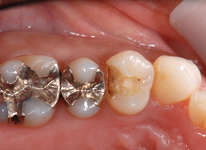

セラミックインレー

昔詰めた銀歯のお色が気になる方や金属アレルギーが心配な方へ

透明で美しく変色しにくい素材をおすすめします。見た目が天然歯に近い素材なので、区別がつきにくく年数がたっても変色しにくいことが特徴です。

Before

After